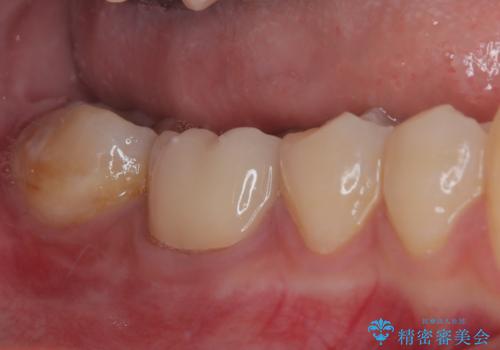

- 奥歯の歯肉から定期的に膿が出てくるとのことで来院された患者様です。

レントゲン写真などの診察を行った結果、根管治療が必要であったため、現在のクラウンを除去し、根管治療を行うこととしました。

根管治療後は症状を確認し、速やかにオールセラミッククラウンにて補綴治療を行うこととしました。